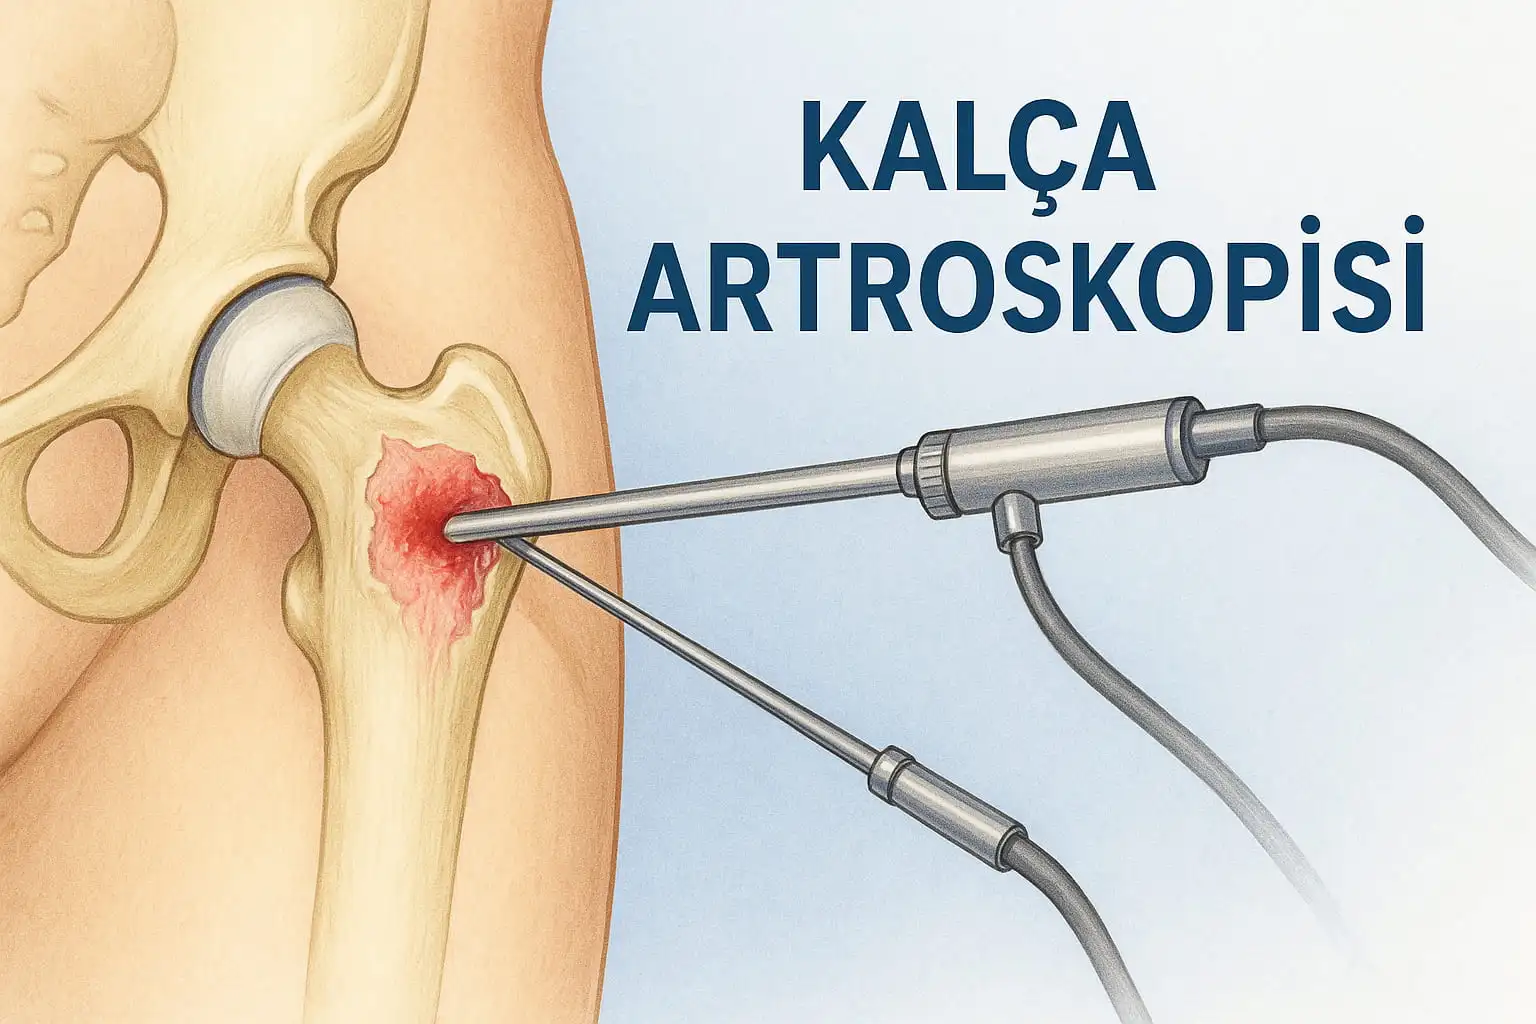

Kalça artroskopisi, kalça eklemi içerisindeki hastalıkların tanı ve tedavisinde kullanılan, minimal invaziv yani kapalı cerrahi bir yöntemdir.